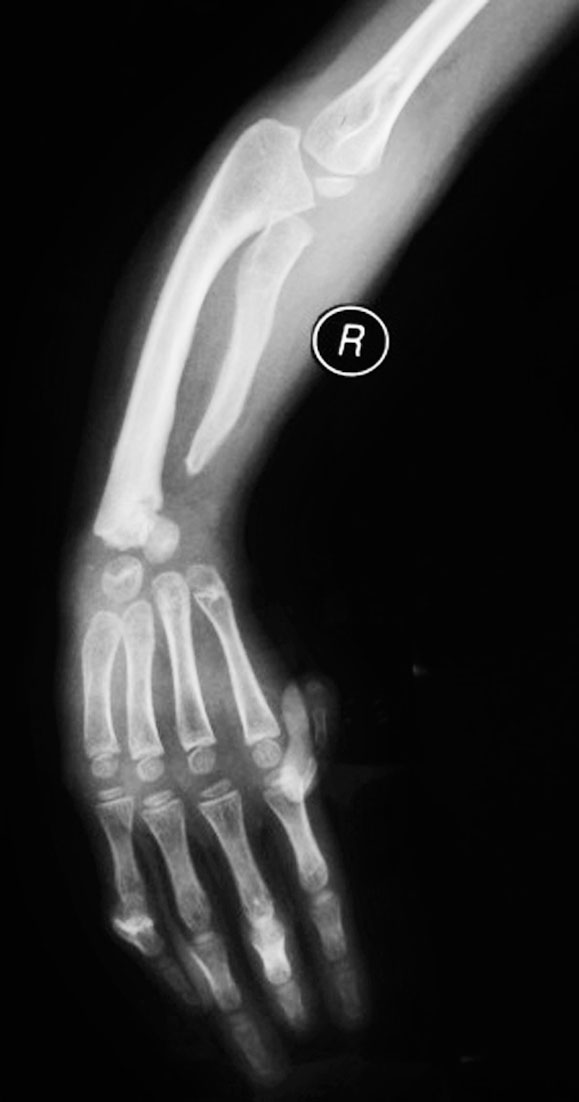

(1)尺骨部分缺如(图1-2-8)。

图1-2-8 尺骨部分缺如

A.左侧前臂尺侧纵列发育不良;B.X 线片显示尺骨远端缺如,桡骨继发性侧弯